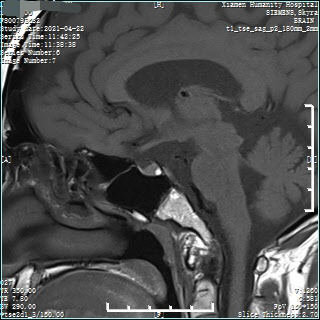

#4检查有条不紊地进行中,相关结果陆续回复,真相也逐渐露出了水面......● 小林的甲状腺功能未见明显异常,皮质醇、ACTH 节律基本正常,最重要的性激素结果显示:促黄体激素(LH)和睾酮水平都明显低于正常值,FSH 位于正常值下限。图 3:性激素六项结果 来源:作者提供● 睾丸彩超提示:双侧睾丸体积明显偏小。图 4:睾丸彩超报告 来源:作者提供● 垂体 MRI 平扫 + 增强显示:垂体未见明显异常。图 5:垂体 MRI 增强来源:作者提供当这些检查结果摆在面前时,我基本上可以肯定之前的判断是正确的。接下来,距离确诊就剩最后一个步骤了——曲普瑞林兴奋试验:给小林肌肉注射曲普瑞林 100 ug,60 分钟后测得 LH 为 2.08 mIU/mL(< 4 mIU/mL),提示性腺轴未启动。曲普瑞林试验最后排除了体质性青春发育延迟,我们最终给小林明确了诊断:特发性低促性腺激素性性腺功能减退症(IHH)。